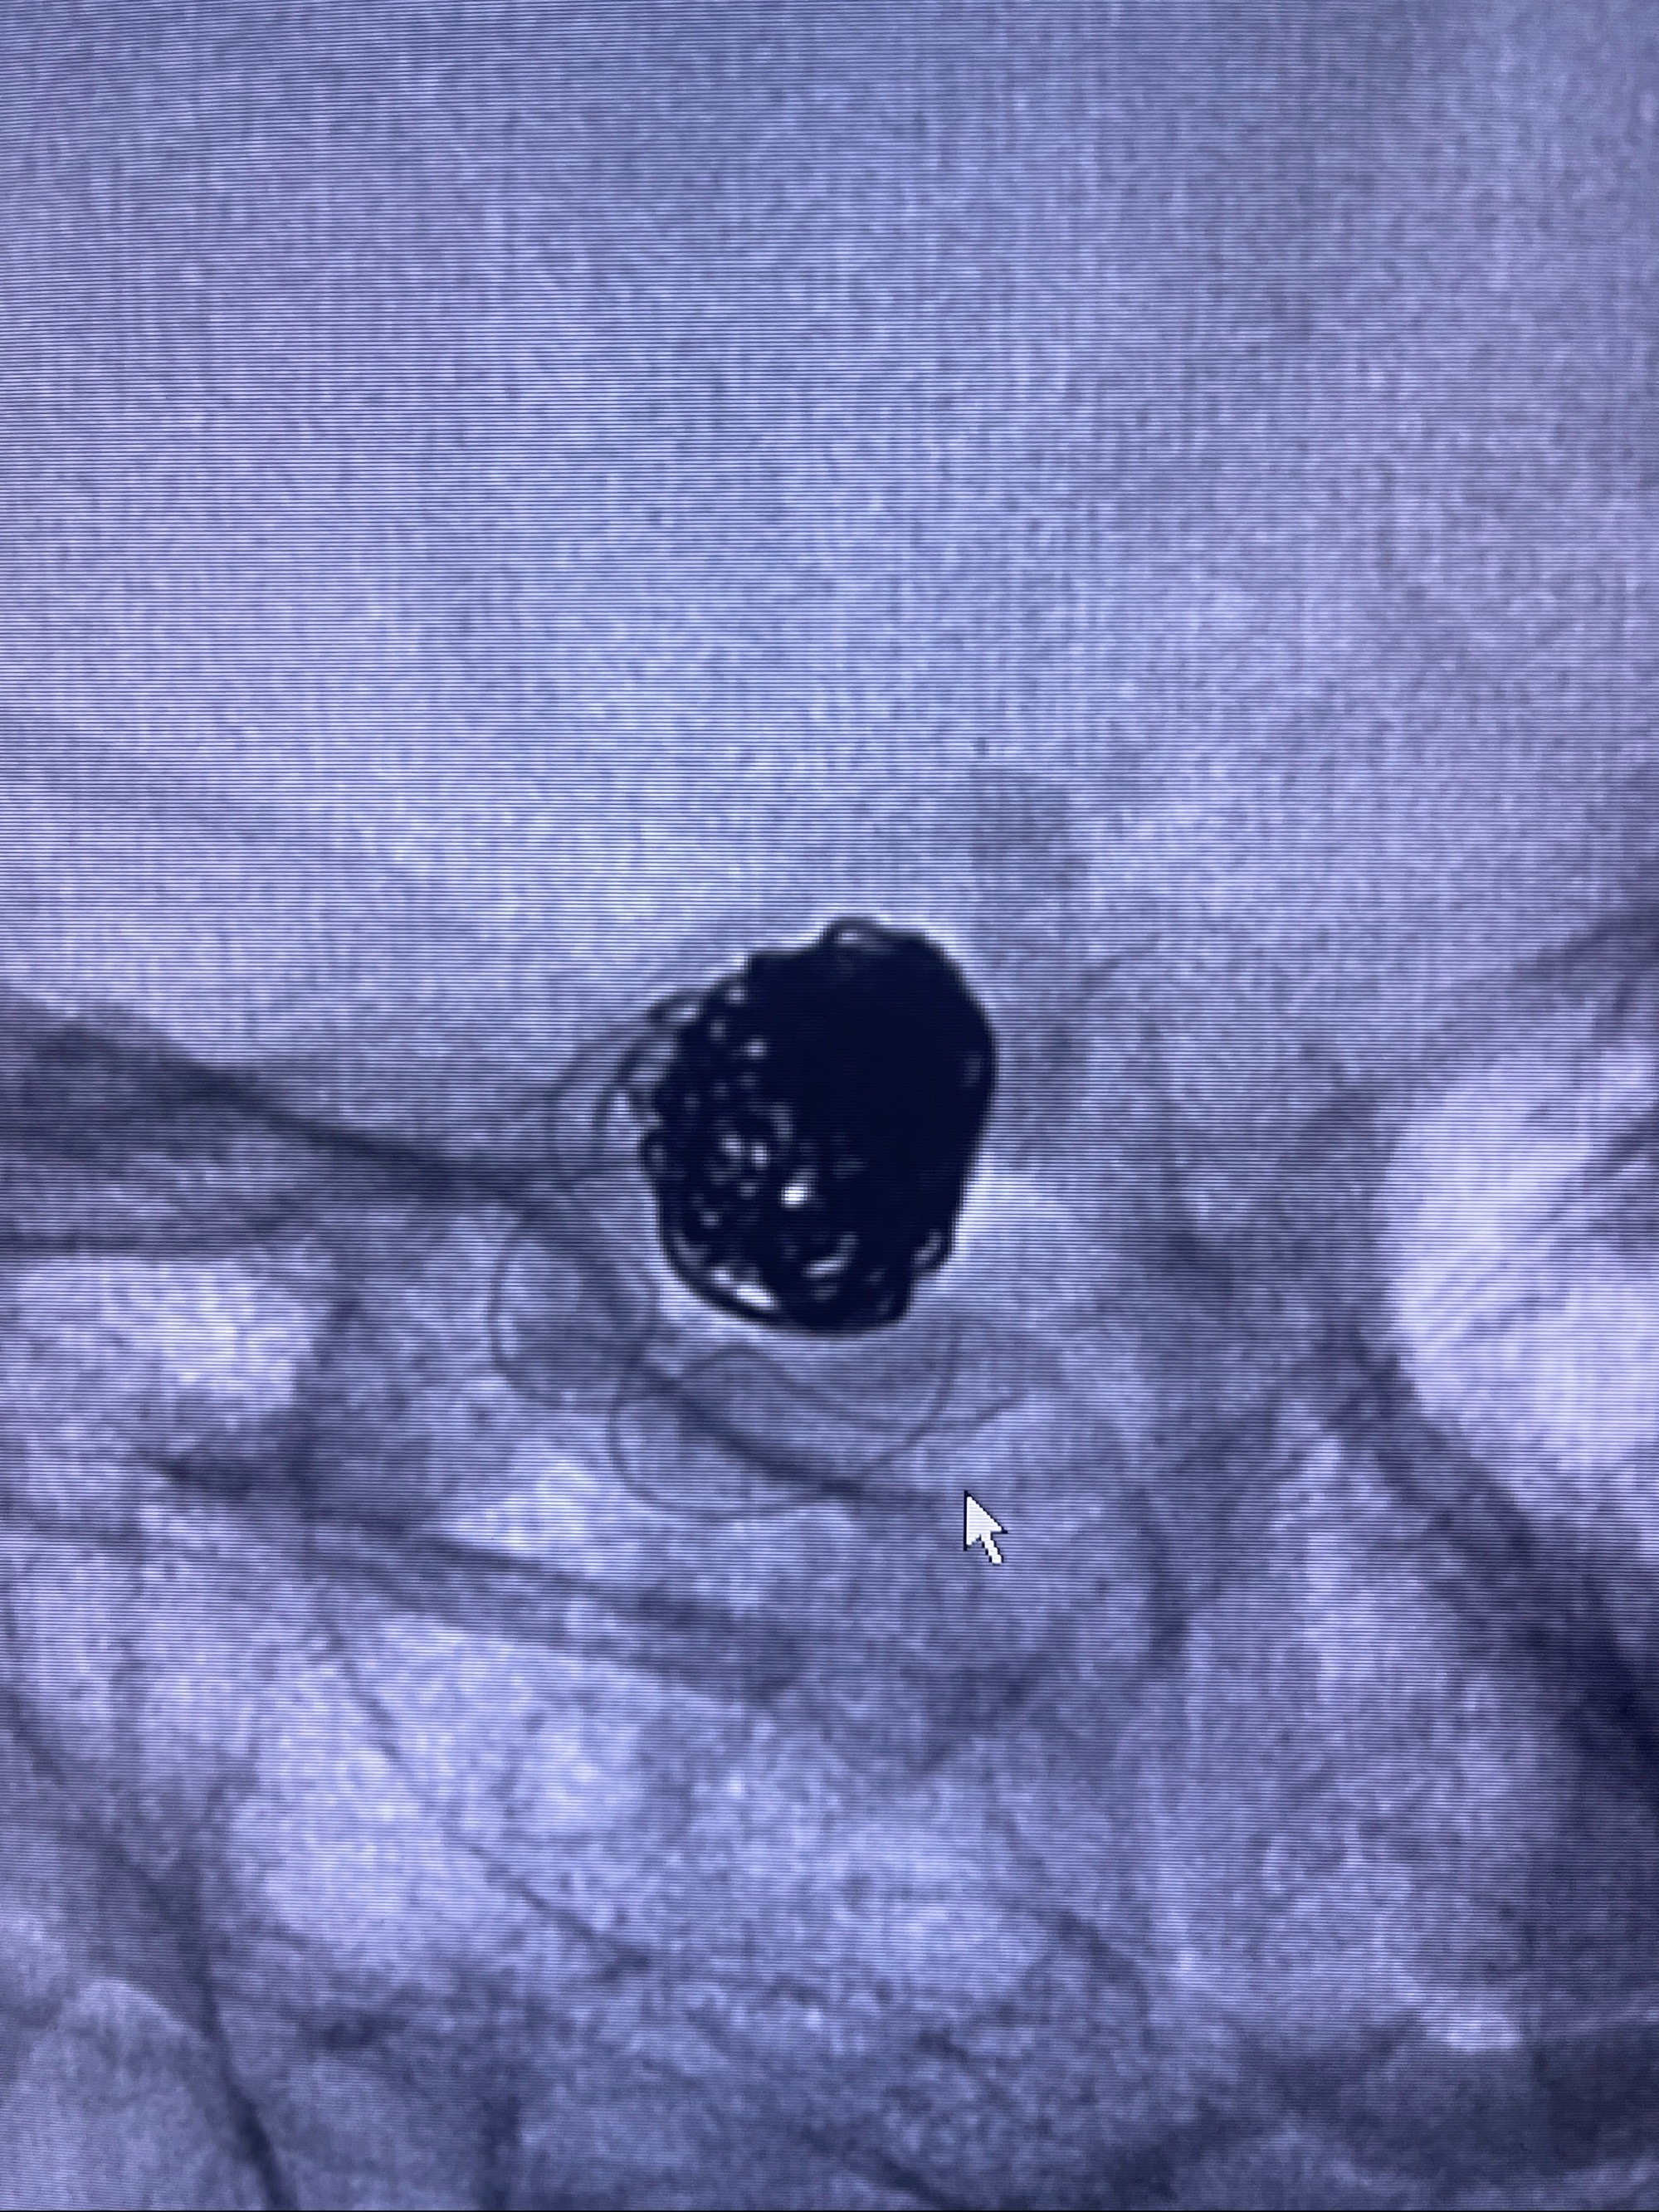

2023-08-30DSA:左侧颈内动脉眼动脉动脉瘤,约3*9.2*7.3mm大小

密网支架辅助栓塞

- Tubridge 4.0-20mm密网支架

- 加奇微弹簧圈:7*30/6*20/5*20/2*8

术后3D显示支架贴壁佳